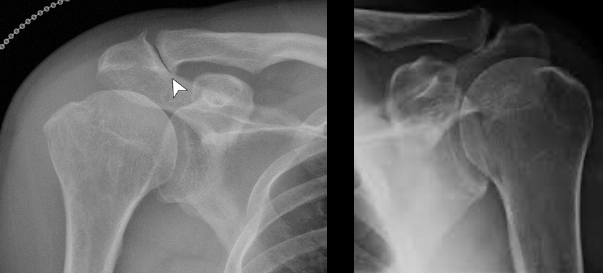

Q

Proyecciones de Rx para ver el desgarro de manguito rotador

• AP

• Oblicua en Y

Datos en Rx que sugieren pinzamiento (lesión)

Desgarro de manguito rotador

• Osteofitos acromioclaviculares

• Disminución del espacio subacromial (< 7 mm)

• Irregularidad de cabeza humeral